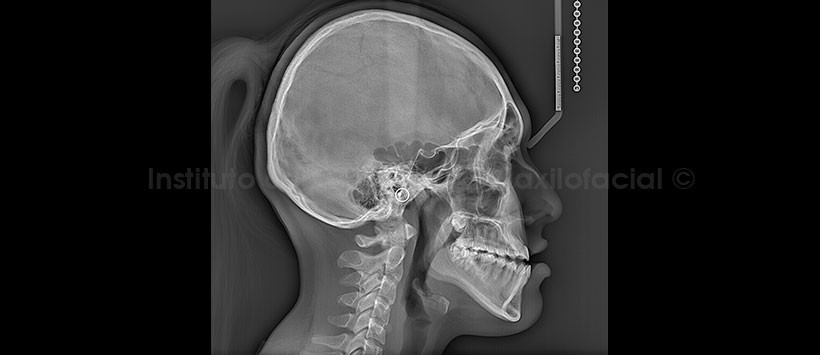

En la radiografía lateral (Figura 2) se aprecia, una imagen radiolúcida, límites definidos y bordes corticalizados, multilocular proyectado a nivel de la base craneal media. Se aprecia además, la neumatización del seno esfenoidal y del seno frontal.